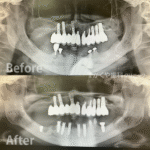

インプラント治療例(80代 女性)_0005

インプラント治療例 「噛み合わせられない/入れ歯が合わない」ということでご来院いただきました。インプラント治療で快適に噛めるようになりました。下顎はロケーターアタッチメント使用しています。 レントゲン画像 実際の見た目の […]